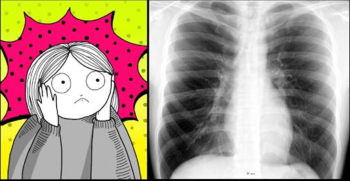

Estas 5 condiciones médicas pueden causar ansiedad

3 min | 19/11/2018